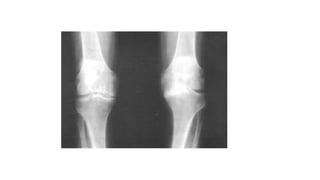

Caso Clínico 2 •Arco de movimento (ADM) encontra-se diminuído moderadamente a direita, com crepitação presente.

A-DIMINUIÇÃO DO ESPAÇOARTICULAR EM PLATÔ MEDIAL B -VISÃO AMPLIADA DO JOELHO DIREITO